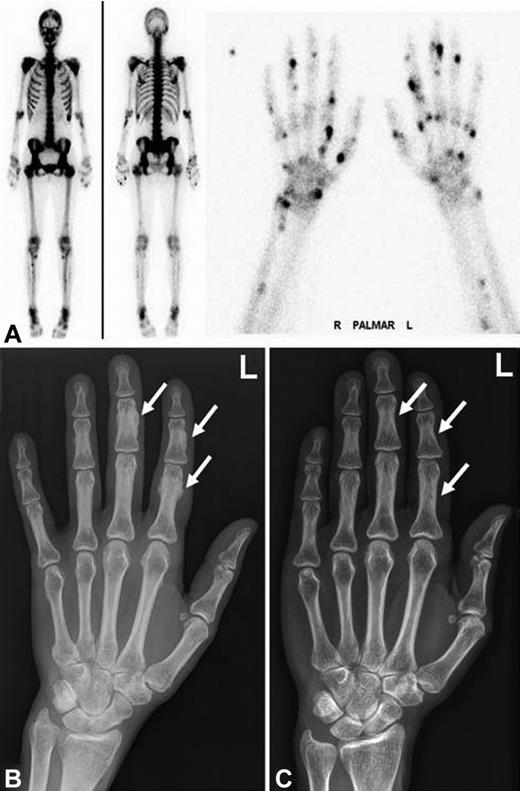

Radiographic findings and bone scintigraphy in patient 2. (A) Plain film showing marked periosteal bone apposition on radial and distal diaphysis of the first metacarpal bone of the right hand (arrow). (B) Technetium 99m-methyl-diphosphonate bone scintigraphy showing marked tracer uptake in the entire skeleton, most pronounced in the spine and pelvis. There are active spots in bones of both hands and feet. (C) CT scan of the entire skeleton revealed bone appositions in various sites of the skeleton (arrows): at the caudal margin of the glenoid (top), at the dorsal ribs (middle), and periacetabular on both sides (bottom). Findings are typical of hypertrophic osteoarthropathy.

We report 3 patients on long-term voriconazole treatment who developed clinically significant skeletal disease, which was completely reversible after termination of voriconazole (Table 1). All 3 patients were female allogeneic stem cell transplant recipients with cyclosporine-related moderate chronic renal failure. Disseminated bone pain started between 3 and 7.5 months of voriconazole treatment. Laboratory findings included an elevated alkaline phosphatase and bone-specific alkaline phosphatase, normal levels of calcium, phosphate, parathyroid hormone, 25-hydroxyvitamin D, and a slightly elevated urinary deoxypyridinoline/creatinine quotient. Conventional radiographs, CT scans, and bone scintigraphy revealed periosteal appositions and focal tracer uptake, respectively (Figures 1 and 2). CT scans of the chest and abdomen showed no signs of secondary malignancies, and bone marrow biopsies ruled out recurrence of the acute leukemia. Patients 1 and 2 were initially misdiagnosed as having an unusual musculoskeletal presentation of GVHD; hence, the immunosuppression was intensified. However, the pain was only temporarily attenuated by corticosteroids and methotrexate but disappeared almost completely in all 3 patients within 4 days of voriconazole cessation. The diagnosis of voriconazole-induced skeletal disease was made only retrospectively in patient 1, 20 months after occurrence of the first symptoms in patient 2, and without delay in patient 3. Serum fluoride measurements at diagnosis were available for patients 2 and 3 with > 10-fold elevated levels and a marked decrease within 3 weeks of voriconazole cessation (81% and 57% of precessation values, respectively). Long-term follow up of 5.5 years after the initial diagnosis revealed complete resolution of the skeletal changes in patient 1 (Figure 1).